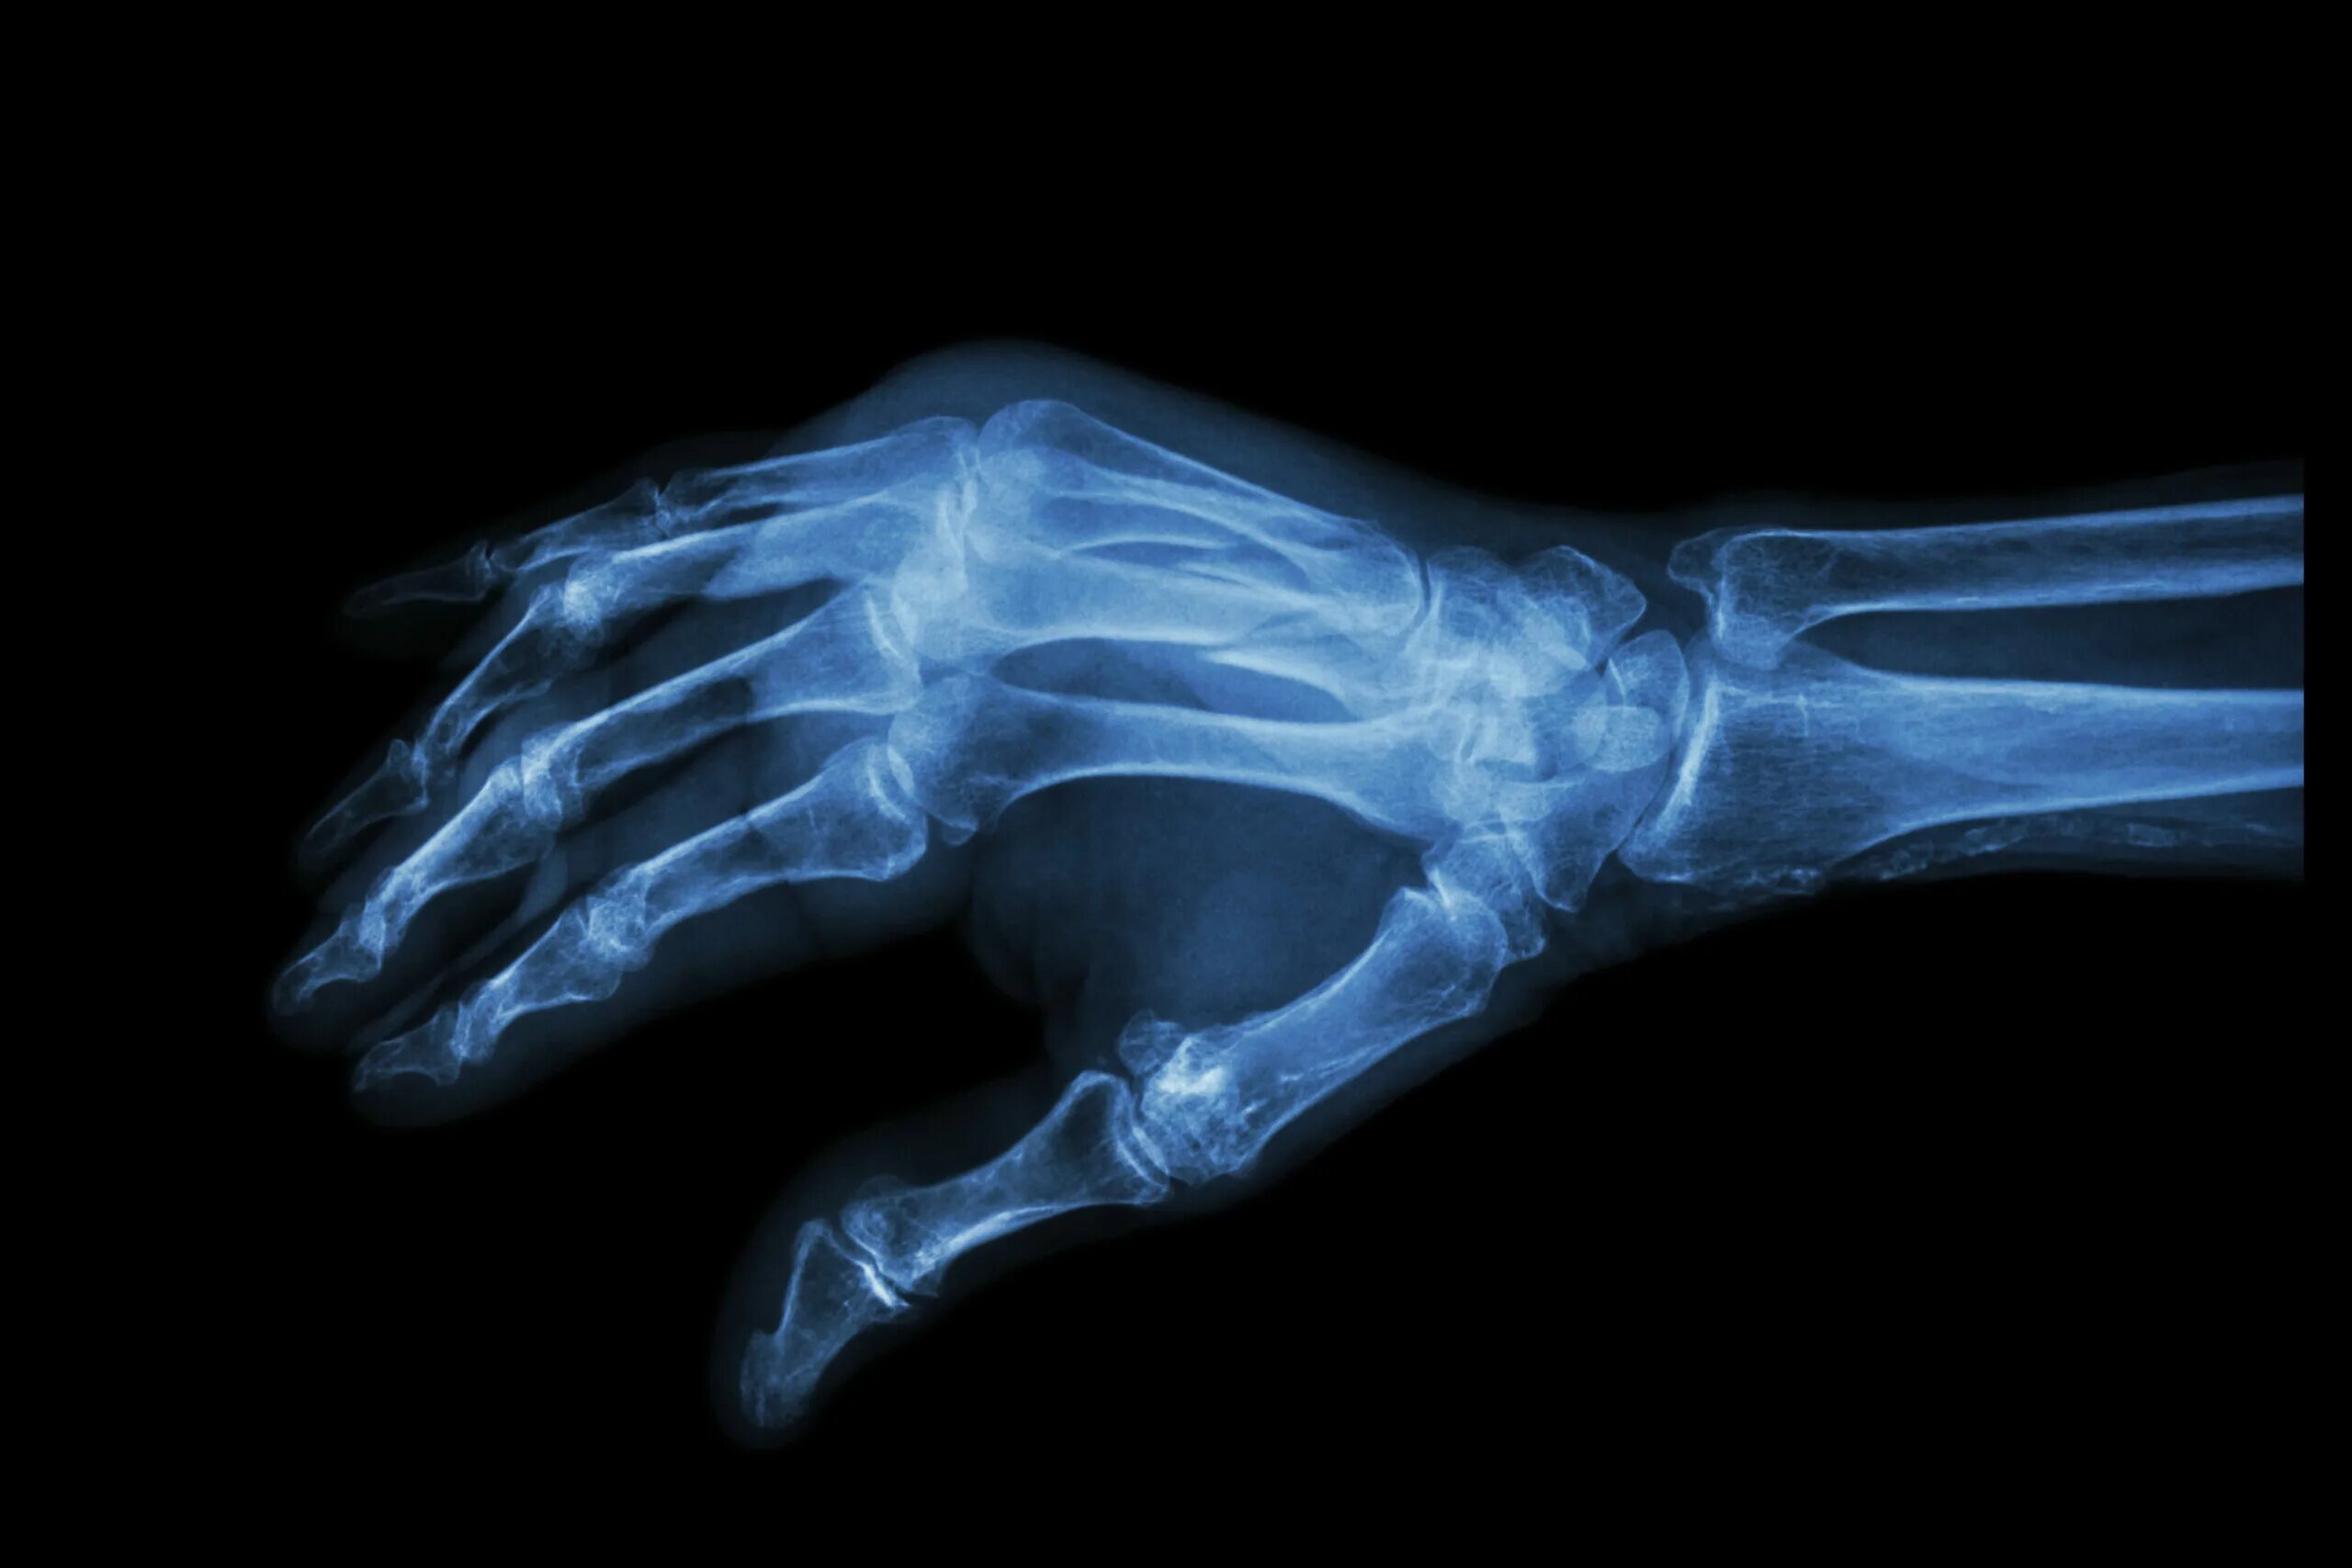

Перелом 3 пястной кости